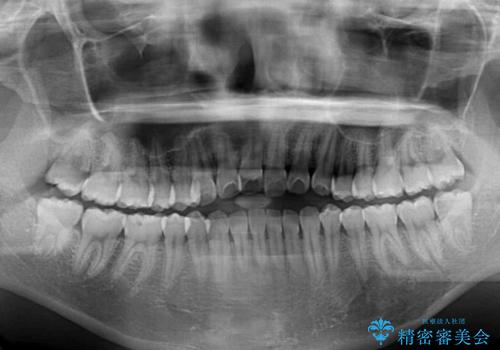

オープンバイトでかみにくい インビザラインによる矯正治療

- 前歯の上下スペースによる食べにくさを気にして来院された患者様です。

インビザラインにより上下の前歯の隙間を閉じていくこととしました。

上下の奥歯を圧下させるようにすることで、前歯を接触させるように計画しました。

上下の隙間に舌が入り込むことがオープンバイトの原因であったため、舌の筋肉のトレーニングも並行して行い、後戻りの抑制を図りました。